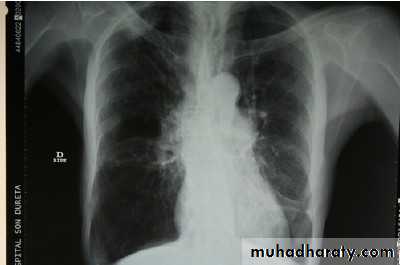

Lung function tests are not accurate during an exacerbation, so their routine use is not recommended.Chest x ray showing signs of hyperinflation